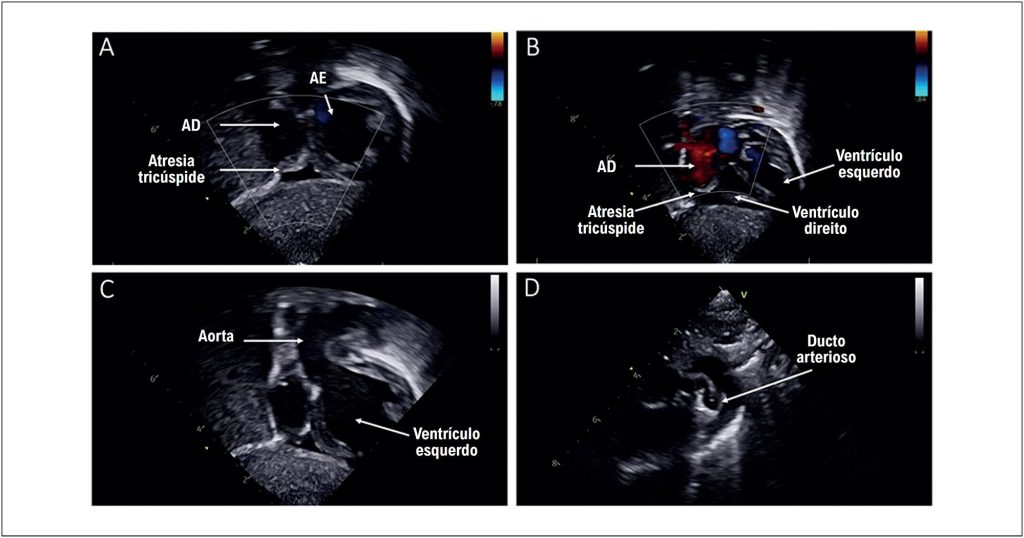

A atresia tricúspide acompanhada de atresia pulmonar é uma cardiopatia congênita rara, representando aproximadamente 1% a 3% de todas as cardiopatias congênitas. A atresia tricúspide é subdividida em tipo I (posição normal das grandes artérias) e tipo II (transposição das grandes artérias), sendo o tipo 1A caracterizado pela presença de estenose ou atresia pulmonar associada. O fluxo sanguíneo pulmonar nesses pacientes depende da persistência do ducto arterioso, tornando sua manutenção essencial no período neonatal.

O tratamento da atresia tricúspide segue uma abordagem cirúrgica em estágios, visando a circulação de Fontan como objetivo final. No período neonatal, o foco é garantir fluxo sanguíneo pulmonar adequado por meio de intervenções hemodinâmicas ou cirúrgicas, incluindo shunts sistêmico-pulmonares ou intervenções no ducto arterioso.